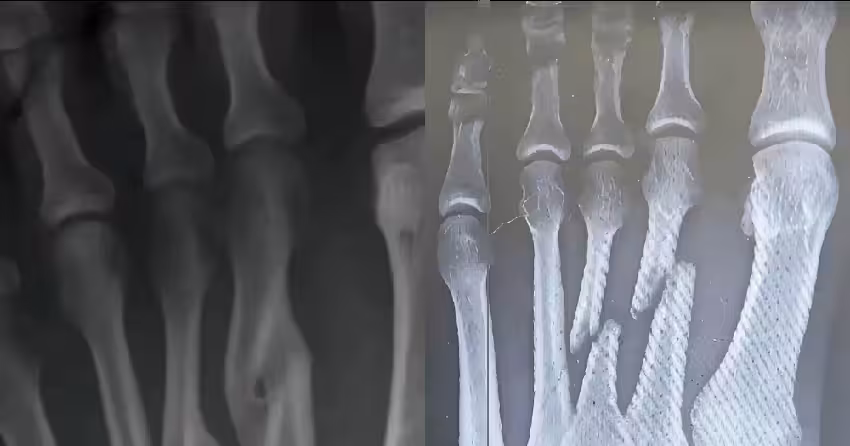

婆婆「摔斷骨頭」拒開刀!全家怕後遺症苦勸不聽…幾個月後醫看X光片也傻了

如今,李阿嬤已能慢慢行走,腳踝上的隆起成為這段經歷的印記。